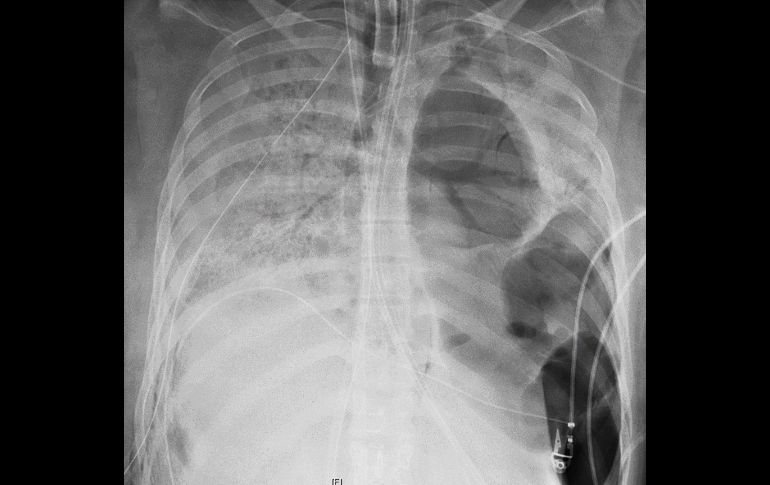

La enfermedad provocó grandes agujeros en su pulmón izquierdo, abriendo la vía a una infección bacteriana. Toma de rayos X de los pulmones de la paciente, antes del trasplante. AP/Northwestern Medicine

La enfermedad provocó grandes agujeros en su pulmón izquierdo, abriendo la vía a una infección bacteriana.